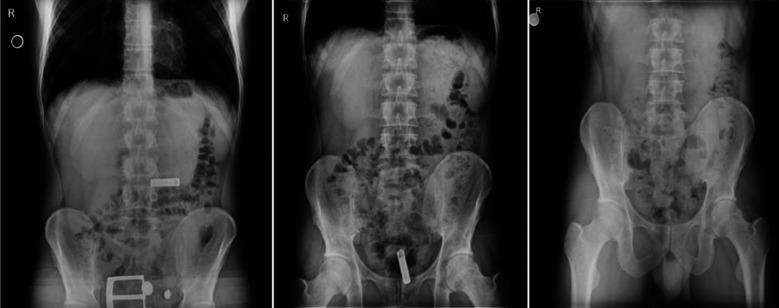

Due to their chemical properties, accidental or suicidal ingestion of batteries into the digestive system can cause fatal complications; Treatment should not be delayed and close monitoring is required. A 26-year-old male patient is treated by the psychiatry department with diagnoses of antisocial personality disorder and depressive adjustment disorder. He consulted with the complaint of ingesting cylindrical AA battery for suicidal purpose. In our case, the cylindrical AA battery in the duodenum was removed from the rectum at the end of the third day without any complications. However, the continuous movement of the cylindrical AA battery with lactulose treatment in the gastrointestinal tract and the support of this movement with abdominal radiographs can reduce the risk of fatal complications. When planning the battery treatment in the gastrointestinal tract, the location of the battery and whether it is mobile should be determined. While obstruction of oesophagus by batteries requires emergency surgical treatment, batteries that remained fixed in the stomach for longer than 48 hours need to be treated with surgical or endoscopic methods.

由于其化学性质,意外或自杀性吞食电池进入消化系统会导致致命并发症;治疗不应延迟,需要密切监测。一名26岁男性患者因反社会人格障碍和抑郁性适应障碍由精神科进行治疗。他因自杀目的吞食圆柱形AA电池前来咨询。在我们的病例中,十二指肠内的圆柱形AA电池在第三天末从直肠排出,没有任何并发症。然而,圆柱形AA电池在胃肠道中通过乳果糖治疗的持续移动以及腹部X光片对这种移动的支持可以降低致命并发症的风险。在规划胃肠道内电池治疗时,应确定电池的位置以及它是否可移动。虽然电池阻塞食管需要紧急手术治疗,但在胃内固定超过48小时的电池需要通过手术或内镜方法进行治疗。